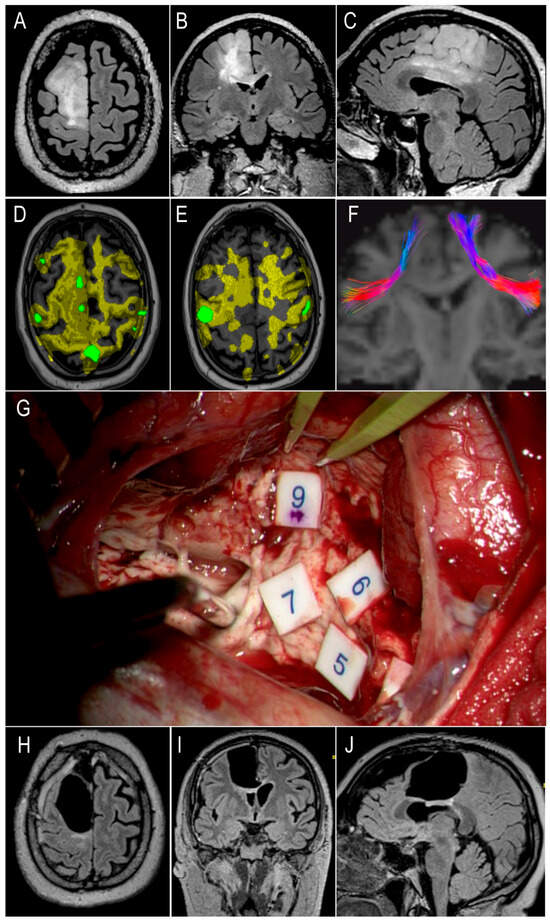

3.8. Illustrative Case